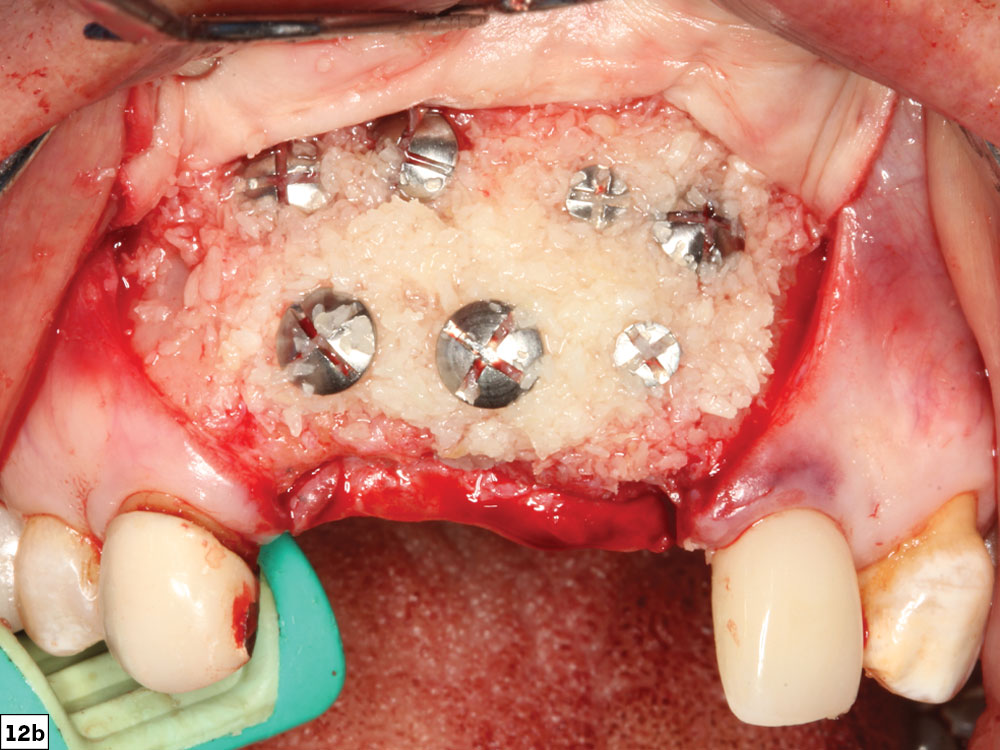

Allogenic bone is the most ideal bone substitute used today for GBR techniques. Allografts are available in many different preparations, with the most common being freeze dried bone allograft (FDBA) and demineralized FDBA (DFDBA). The recommended graft material (e.g., Newport Biologics™ Mineralized Cortico/Cancellous Allograft Blend [Glidewell]) should be hydrated with sterile saline (0.9% sodium chloride) or platelet-rich fibrin (PRF) and then gently condensed into the recipient site. Small increments of material should be added into the site, and a bone-packing instrument, such as the Bone Carrier and Spoon included with the 12-piece Newport Surgical Implant and Bone Grafting Instrumentation Kit (Glidewell), should be utilized to condense the material to avoid air spaces (Figs. 12a, 12b).

Newport Biologics Mineralized Cortico/Cancellous Allograft Blend

Material of the cortico/allograft is added using bone-packing instrument

Figures 12a, 12b: Newport Biologics Mineralized Cortico/Cancellous Allograft Blend (12a); graft material added to recipient site (12b).